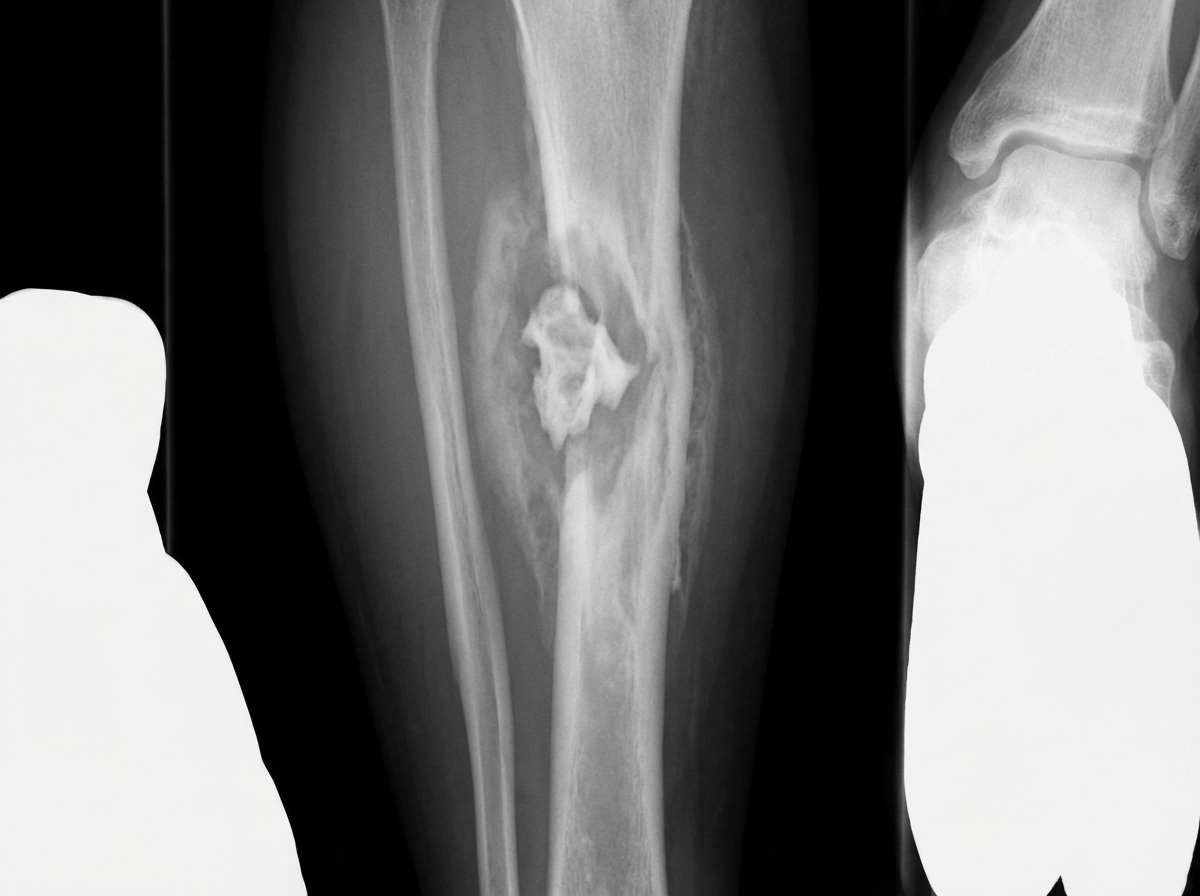

A patient with a history of Road Traffic Accident (RTA) two years ago developed pain and swelling at the same site in the leg. X-ray shows certain features. What is the most likely diagnosis?

Explanation: ***Chronic osteomyelitis*** - History of **Road Traffic Accident** two years ago provides a predisposing factor for bone infection through **open fracture** or **contamination**. - X-ray findings typically show **sequestrum** (dead bone), **involucrum** (new bone formation), **sclerosis**, and **periosteal reaction** consistent with chronic infection. *Osteogenic sarcoma* - Most common in **adolescents** and young adults, typically presenting as a **primary malignancy** without clear traumatic history. - X-ray shows **sunburst pattern**, **Codman's triangle**, and **soft tissue mass**, which differ from post-traumatic chronic infection changes. *Ewing's sarcoma* - Predominantly affects **children and adolescents** under 20 years, with no clear association to trauma. - Characteristic X-ray findings include **onion-skin appearance** with **permeative bone destruction** and extensive **soft tissue involvement**. *Multiple myeloma* - Typically occurs in **elderly patients** over 60 years and presents as **multiple lytic lesions** throughout the skeleton. - Associated with **systemic symptoms** like anemia, hypercalcemia, and renal dysfunction, not localized post-traumatic pain.